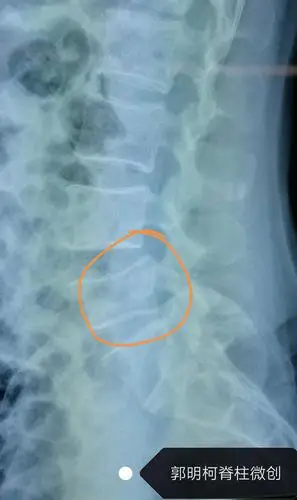

司机跌倒造成腰椎椎弓两处骨折非侵入性水介质震波让骨愈合